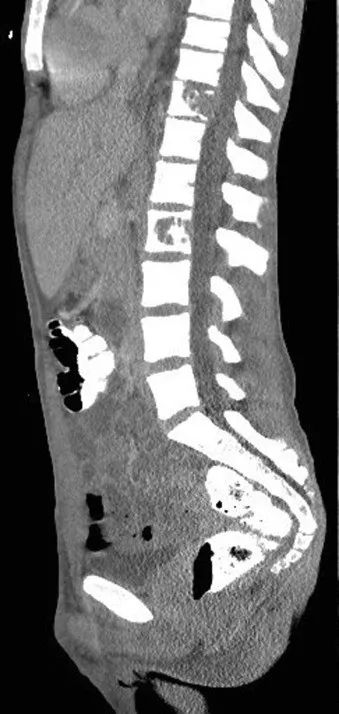

全血白细胞计数为13.4*109/L,血红蛋白8.5g/dL,血小板138/μL,C-反应蛋白28.8(正常值<3.0)。动脉血气分析显示pH值为7.30,PCO2为48.2,PO2为71.8,血培养呈阴性,进行BAL培养(包括细菌培养、病毒培养、真菌培养)。胸部X线及胸部CT显示弥漫性斑片状阴影(图1.2)。颈椎、胸椎和腰椎的CT扫描显示椎体病变(图3.4)。由于脾脏有多处病变,也进行了脾活检(图5)。

图4 腰椎CT:T11和L2椎体破坏性病变